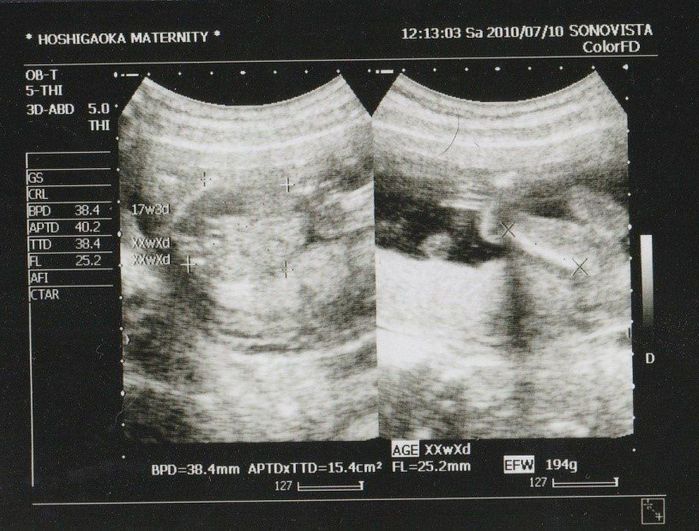

妊娠17週目のエコー写真

右側のエコー写真には、お尻と脚が2本写っています。このエコー検査から「性別は女の子かもしれない」と主治医の先生から言われた思い出の一枚です。そして、大腿骨の長さや頭の左右幅から割り出した推定体重から、「大きめだね!」と言われ始めたのもこの頃。しかし、大きく成長していたのは我が子だけでなく、私も“体重増えすぎ印”の赤線を引かれてしまいました。